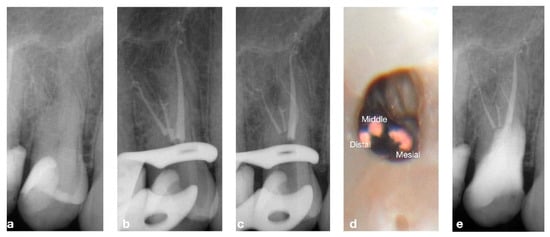

2.2. CASE 2